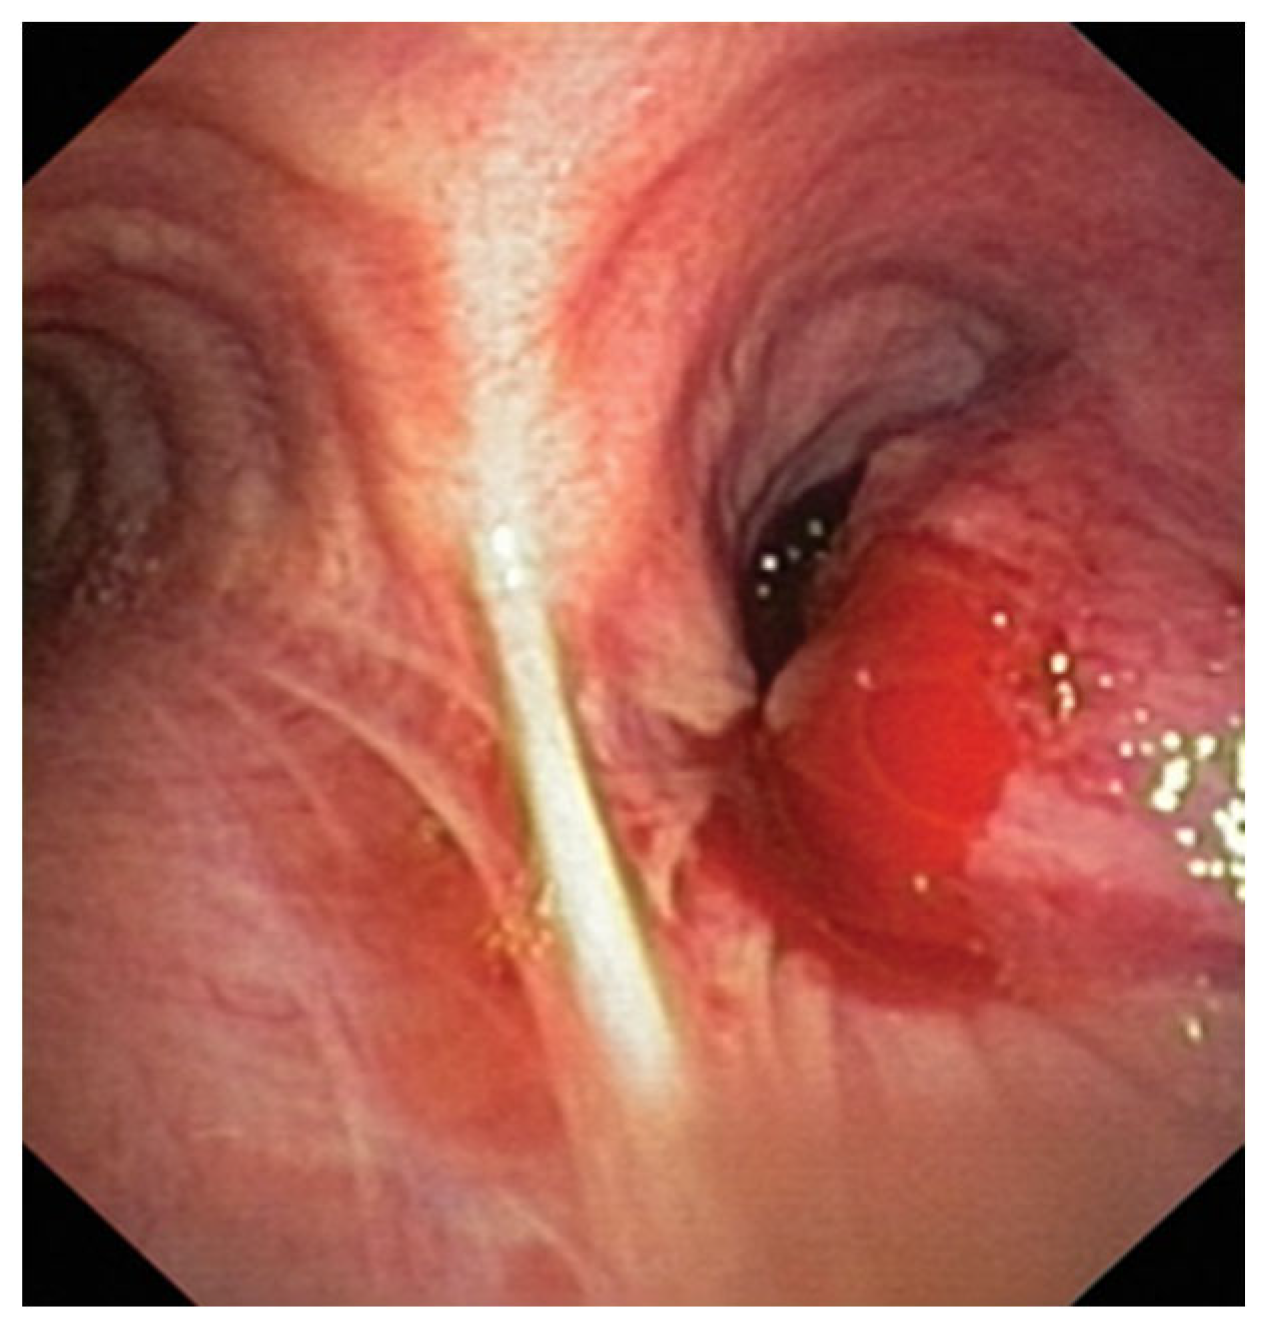

2.1. Cryobiopsy for Endoscopy Visible Tumor Lesions and Transbronchial Cryobiopsy for Peripheral Tumor Lesions—Application of Molecular Tests

2.2. Radial Probe—Endobronchial Ultrasound with a Guide Sheath in the Diagnosis of Peripheral Lung Lesions

RP-EBUS-GS—Guided Endobronchial Ultrasound in the Era of Molecular Testing of Tumor Tissue